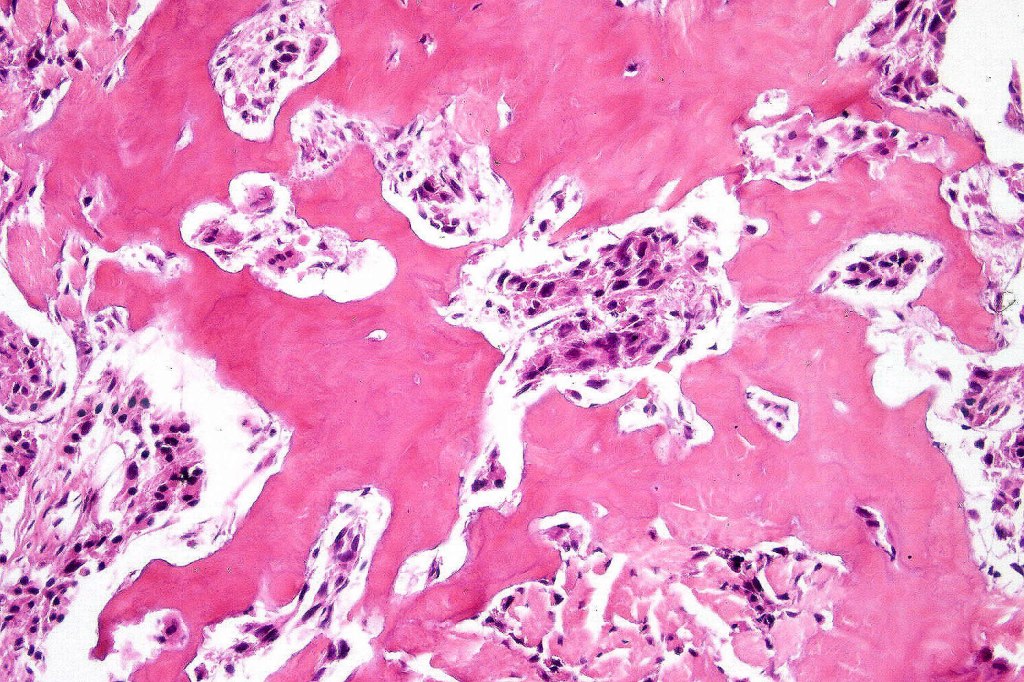

Melanoma with osteoid and chondroid (benign or malignant) are most often encountered in the digits particularly the thumb and large toe, for the other types, they are too rare to make any meaningful clinical comments. Documented heterologous elements include: